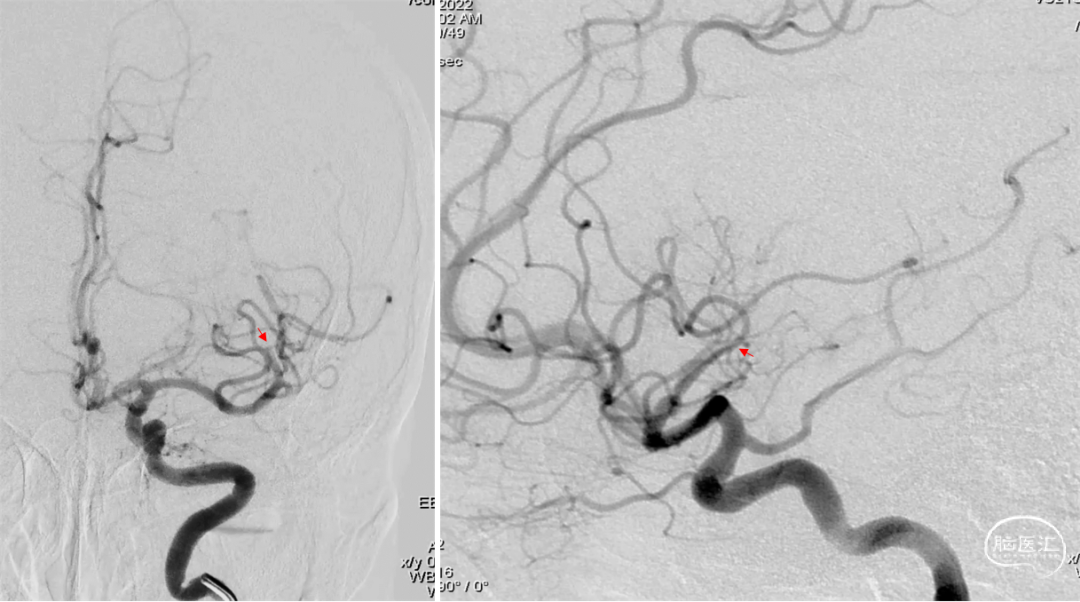

颈内动脉造影提示颈内动脉颈段迂曲,大脑中动脉下干M2远端闭塞,颞顶部可见乏血管区。

在NeuronMAX支撑下,微导丝/微导管辅助4MAX抽吸导管到位,进行抽吸。